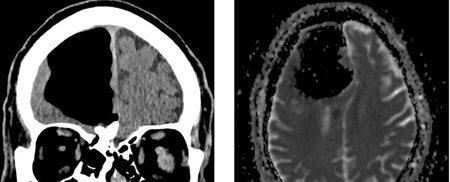

بر اساس گزارش ساینس الرت، تصاویر سیتیاسکن مغز این بیمار نشان داد، بخش بزرگی از لوب پیشانی راست مغز مرد ناپدید شده است.

نتیجه سیتیاسکن گیجکننده بود، حفرهای بزرگ و سیاه به وسعت 9 سانتیمتر در لوب پیشانی سمت راست مرد دیده میشد. در مرحله بعدی مغز مرد با دستگاه MRI مورد بررسی قرار گرفت و پزشکان دریافتند ماده مغزی در جمجمه بیمار ناپدید نشدهاست، بلکه درون جمجمهاش حفرهای از هوا به نام پنوماتوکوئل ایجاد شدهبود که معمولا در بیمارانی دیده میشود که دچار آسیبدیدگی صورت یا عفونت تنفسی شدهاند یا در جمجمه آنها جراحی انجام شده است.